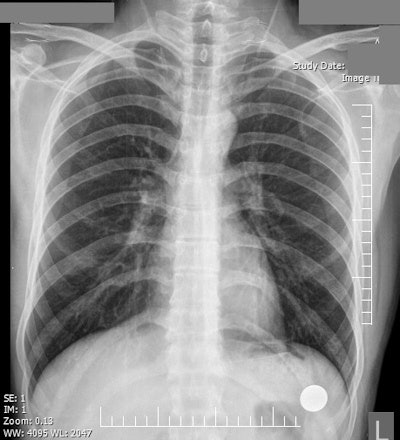

The survey included nine hypothetical clinical vignettes, each associated with a chest x-ray that showed only a single acute chest pathology. For example, a vignette for a patient with dyspnea and pleuritic chest pain contained a classic image of pneumothorax. The researchers further added a low-risk vignette associated with a normal chest x-ray. They asked participants to read each of the 10 vignettes, look at the chest x-rays, and type in the pathology they believed they saw. Also, they asked them to state their confidence in the diagnosis and indicate any prior exposure to the topics.

Overall, the highest rate of correct diagnosis was for diaphragmatic herniation (77%), followed by pneumoperitoneum (67%) and pneumothorax (54%). The lowest rate of correct diagnosis occurred for acute respiratory distress syndrome (ARDS) (8%), foreign body (12%), and the low-risk vignette associated with the normal chest x-ray (15%). The key findings are shown on the table below.

Normal | 15 | 13 | 44 |

Most participants failed to diagnose the majority of acute pathologies with diagnostic clues on chest x-ray, according to the researchers. Furthermore, the vast majority (85%) had trouble identifying the normal chest x-ray as being normal, with less than half reporting to have seen it before. Significant knowledge deficiency was deemed to be the main source of errors.